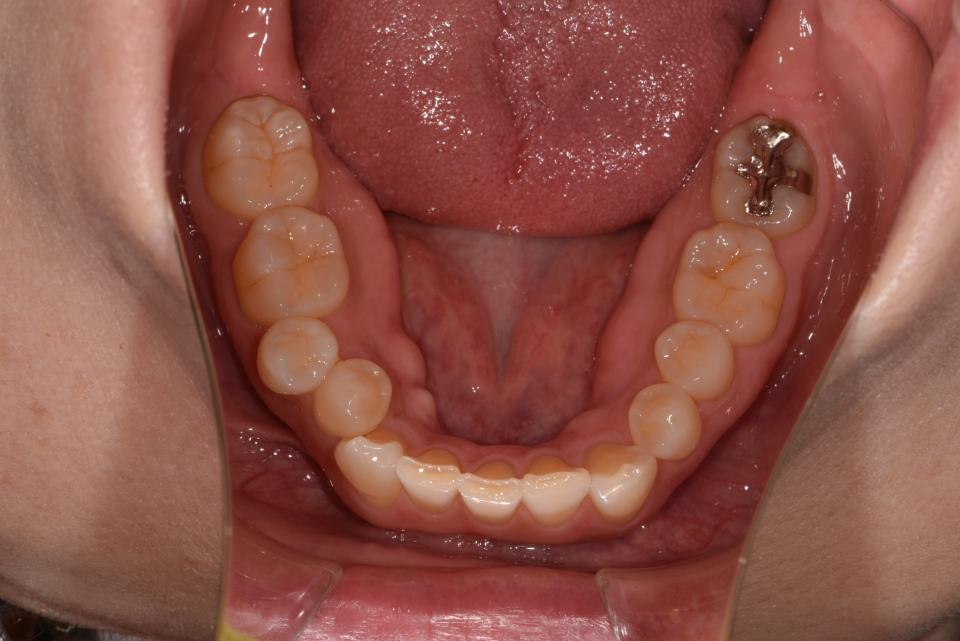

矯正治療前

上の左右4番目の抜歯をして、マウスピース型の矯正治療装置を使用し、歯のやすり掛け(IPR)を行いました。

現在はマウスピース型のリテーナーでで後戻りの防止をして定期的にチェックをしています。